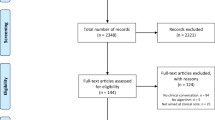

A team of resident doctors in internal medicine, physiatry, anatomical pathology and family medicine, and senior Canadian medical students created this dataset. The medical interviews were recorded in the format of Objective Structured Clinical Examinations (OSCE) 1 . 272 cases were simulated between the physician and the patient. These cases were recorded and classified into the categories of respiratory, musculoskeletal, cardiac, dermatological, and gastrointestinal diseases. However, the majority of simulations were respiratory cases. Please see Fig. 1 for a visual representation of the types of cases included. These audio recordings were then transcribed, manually corrected for speech to text errors, and an identifier was added to specify the speaker.

272 cases were simulated and recorded (please refer to Fig. 1 ). The focus of the dataset was respiratory cases (214 cases). In addition, 46 musculoskeletal cases, 5 cardiac cases, 6 gastrointestinal cases and 1 dermatology case were also simulated. Of the total simulated recordings, 57% of the cases involved a male physician and 43% involved a female physician. From the patient perspective, 55% of the simulated cases involved a male patient and 45% involved a female patient. The average duration of each conversation was 11 minutes and 56 seconds. For further details, please refer to Fig. 2 for a histogram of the number of cases corresponding to various lengths of time. The focus was on respiratory cases because most pandemics, including the COVID19 pandemic, are caused by droplet or airborne based respiratory diseases. Therefore, it is crucial to differentiate between a benign cause of malaise such as the common cold from a highly infectious and fatal cause such as COVID19 or Tuberculosis.